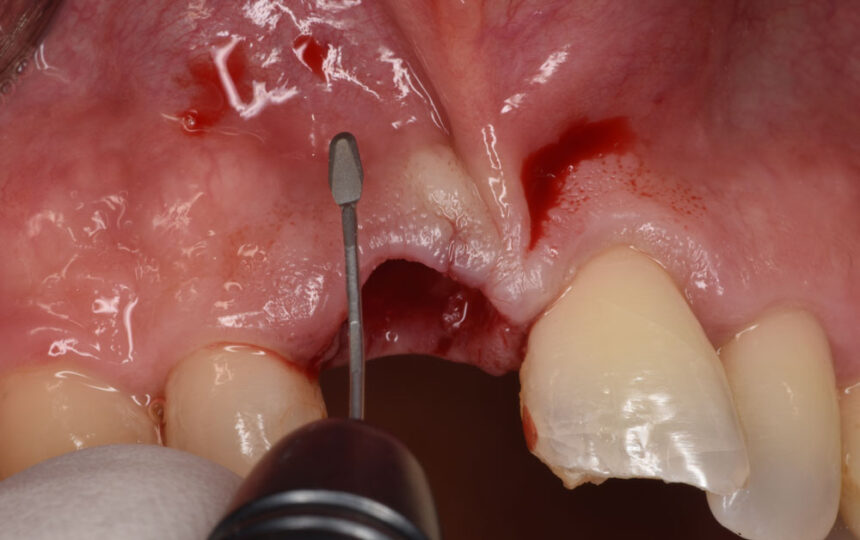

Στο περιστατικό που θα αντιμετωπιστεί live θα γίνει άμεση τοποθέτηση εμφυτεύματος με πλήρη καθοδήγηση χειρουργικού νάρθηκα, θα συζητηθούν οι εναλλακτικές προσεγγίσεις και θα παρουσιαστεί ο τρόπος και τα διαφορετικά σενάρια εξατομίκευσης της επούλωσης των μαλακών ιστών.

- Τεχνικές ατραυματικής εξαγωγής

- Παρουσίαση του πρωτόκολλου τρυπανισμού και ελέγχου με το νάρθηκα κατευθυνόμενης τοποθέτησης,